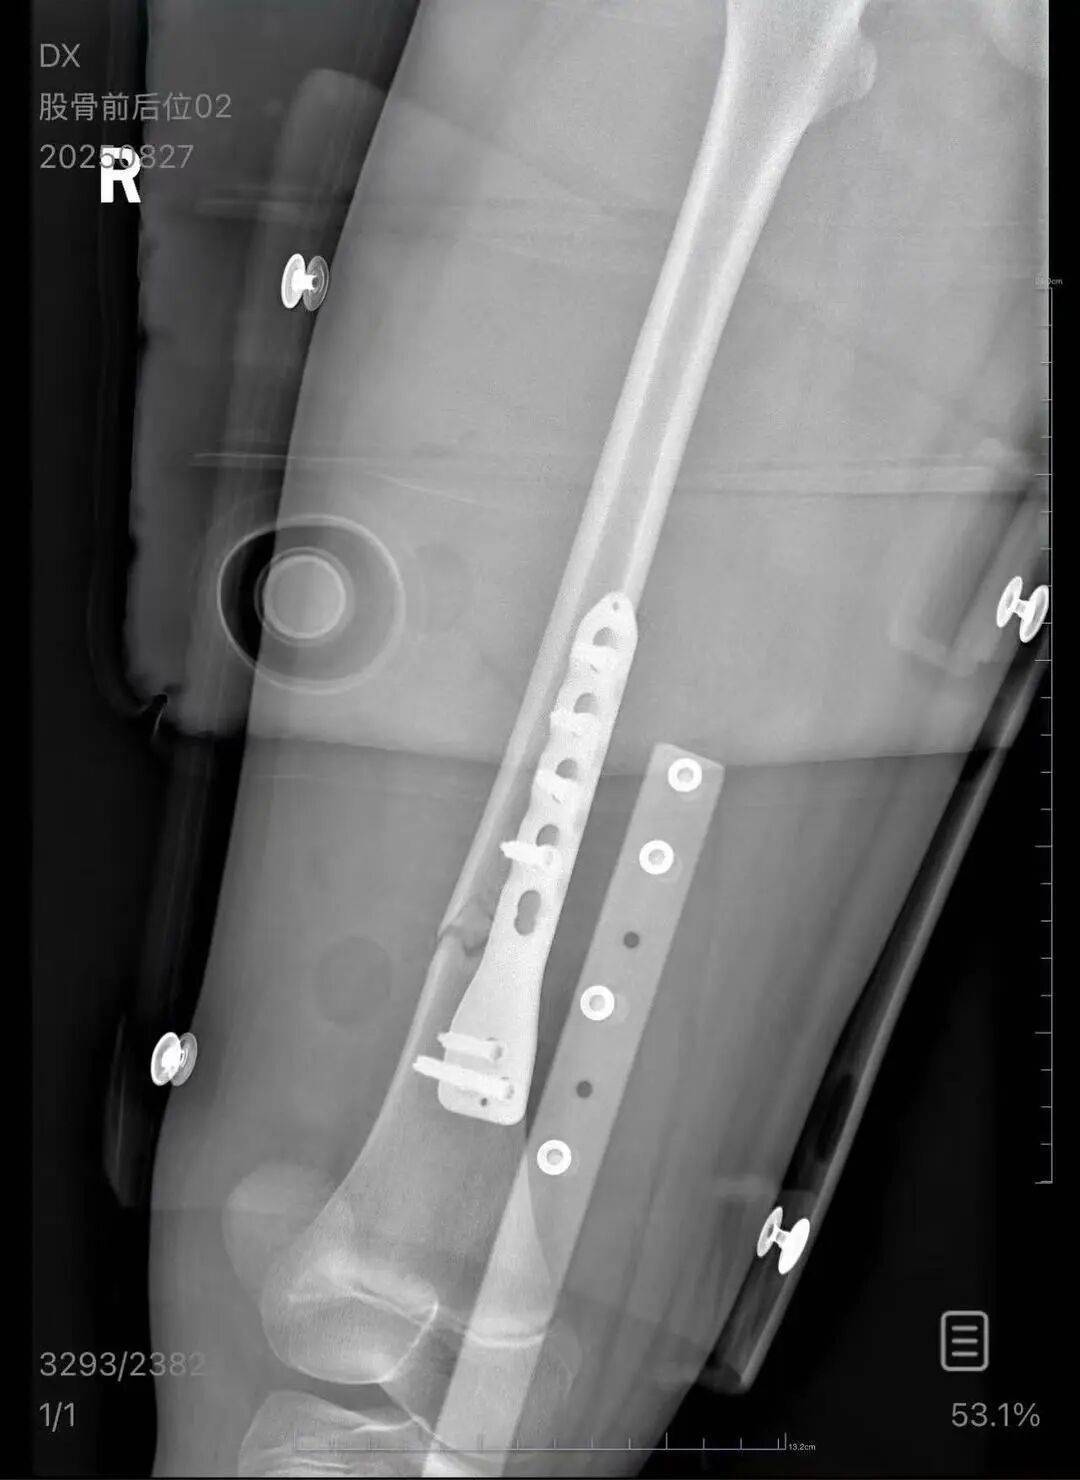

朱女士向记者出示的医院病历显示,8月24日凌晨,朱女士的女儿到医院就诊法币。医院诊断朱女士的女儿右股骨骨折,需要住院进一步治疗。

▲朱女士女儿手术后拍的X光片 受访者供图